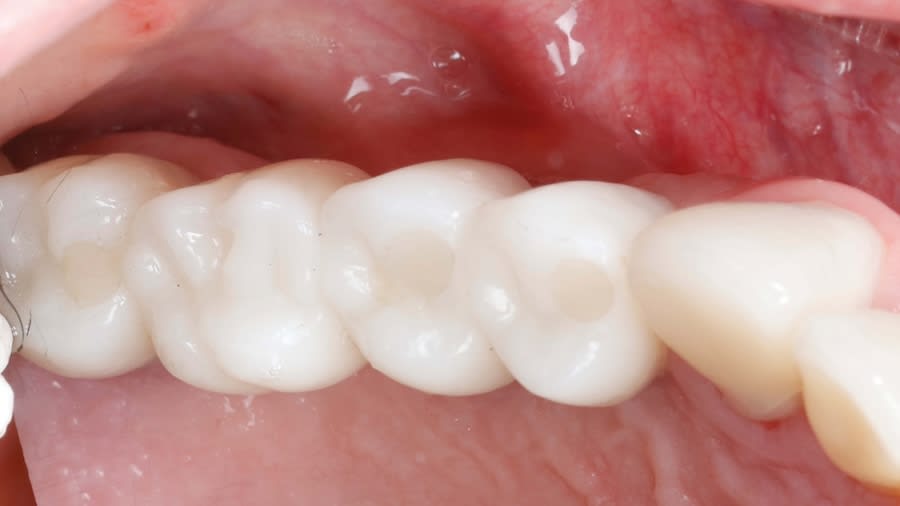

Case 1 (Figure 3 through Figure 24) depicts a 3-year follow-up of combined osseodensification sinus protocol IV in a severely resorbed maxillary ridge with ≤0.5 mm bone height in molar sites and horizontal deficiency at the first premolar site, using a two-stage approach for implant placement.